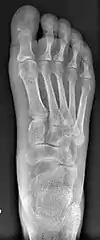

Syndesmosis procedure addresses specifically the two fundamental problems of metatarsus primus varus deformity that gives rise to the bunion deformity. They are leaning and instability of the first metatarsal bone . Syndesmosis procedure uprights the leaning first metatarsal bone with strong binding sutures between it and the second metatarsal bone (Fig. 2) and then also stabilizes it uniquely by creating a fibrous connecting bridge between these two bones (Fig. 3, 4). First metatarsal bone can be readily realigned because by definition of the metatarsus primus varus deformity its first metatarsal is abnormally loose and mobile.